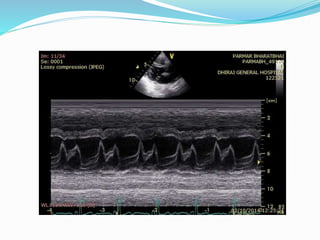

Doppler findings:

 Superior Vena Cava: Diastolic Flow Velocity > Systolic Flow

Velocity

 Hepatic vein: Exaggerated diastolic flow reversal after onset of

expiration.

 Pulmonary Venous Flow: Increase in diastolic flow velocity on

expiration. Systolic/Diastolic flow velocity ratio < .65

 Peak Diastolic flow velocity falls 40% on inspiration.

 Mitral inflow pattern: During onset of exhalation – 25%

increase in early diastolic flow velocity